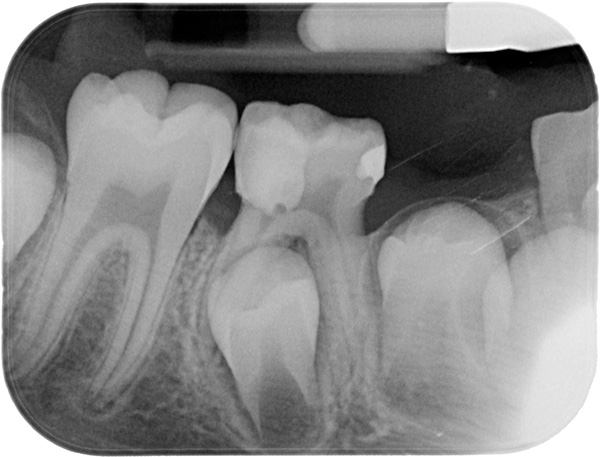

- Studia un'immagine panoramica delle mascelle per valutare la posizione dei denti, l'inclinazione delle radici dei denti, valuta le condizioni dei tessuti adiacenti - il seno mascellare, il processo alveolare della mascella superiore, il canale mandibolare; è anche importante analizzare la placca ossea, che è lo strato tra i denti e le ossa della mascella;